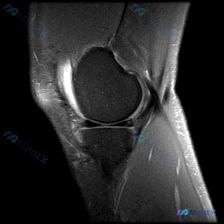

最近碰到一个有意思的读片病例:用户提供了一张膝关节MRI矢状位T1加权图像,主诉提示存在半月板异常,咱们一起来看看这个病例,整理一下思路。 病例核心信息 本次仅提供单张膝关节矢状位T1加权MRI,阅片可见: 1. 骨骼结构:股骨远端、胫骨近端骨皮质连续,骨髓信号符合正常脂肪信号分布,无局灶性异常低信...

看到一个很有代表性的读片病例,怀疑半月板异常但单张T1加权MRI没有发现明确问题,整理了分析思路和大家分享。 病例核心信息 问题:临床怀疑半月板异常,提供单张膝关节矢状位T1加权MRI,需要做影像观察和分析 影像系统性观察结果 1. 骨性结构:股骨远端、胫骨近端、髌骨轮廓规整,骨髓信号正常,未见骨质...

今天看到一份很有代表性的读片病例,整理出来和大家分享一下,核心问题就是:临床怀疑半月板异常,但是只给了一张膝关节矢状位T1加权MRI,阅片没发现明确异常,这个情况该怎么分析? 先整理一下这份影像资料的基本信息 这是单张膝关节正中矢状位T1加权像,图像质量清晰,没有运动伪影,能看到股骨远端、胫骨近端、...